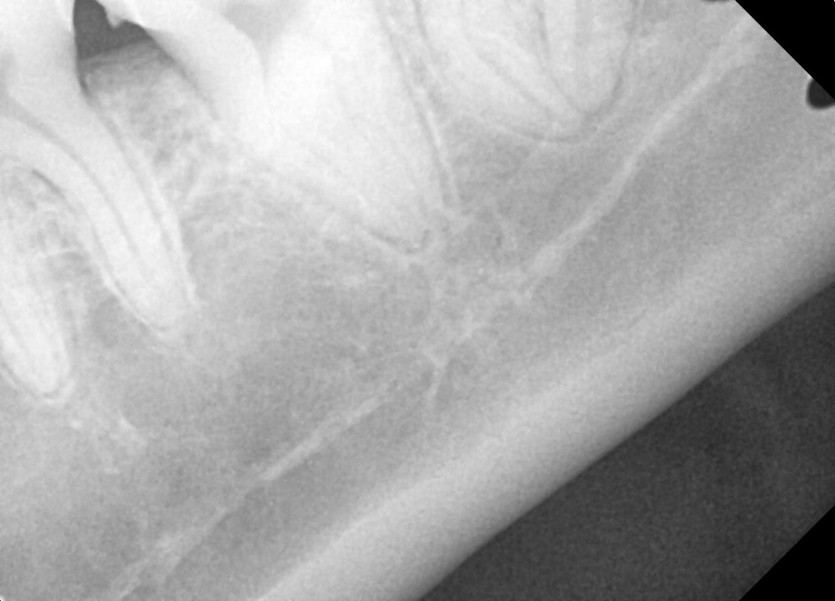

#38 사랑니 발치

구강 외과 전문의가 당일 발치했습니다.